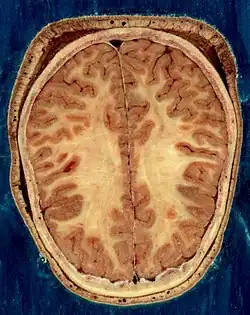

Строение головного мозга

Объём мозга большинства людей находится в пределах 1250—1600 кубических сантиметров и составляет 91—95 % ёмкости черепа. В головном мозге различают пять отделов: продолговатый мозг; задний, включающий в себя мост, мозжечок и эпифиз; средний; промежуточный; и передний мозг, представленный большими полушариями. Наряду с приведённым выше делением на отделы, весь мозг разделяют на три большие части:

Кора большого мозга покрывает два полушария головного мозга: правое и левое.

Полушария большого мозга извне покрыты серым веществом, образующим кору большого мозга, или плащ. В коре насчитывается 15 млрд клеток, а если учесть, что каждая из них имеет от 7 до 10 тыс. связей с соседними клетками, то можно сделать вывод о гибкости, устойчивости и надёжности функций коры. Поверхность коры значительно увеличивается за счет борозд и извилин. Кора филогенетическая является самой большой структурой мозга, её площадь примерно 220 тысяч мм2.